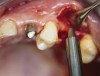

A 53-year-old female was referred for evaluation of a fracture of tooth No. 24. The tooth had been treated endodontically 5 years prior. The radiograph revealed a complete fracture of the tooth involving the crown (Figure 12). Tooth extraction and immediate placement of a an implant that was 10 mm in length and 3.75 in diameter was planned.

At the time of surgery, the tooth was extracted without harvesting any mucosal flap because the implant site was prepared by means of a pilot drill bur (Figure 13) and alternating osteotomes (Figure 14A and Figure 14B). The implant was positioned and showed primary stability. The implant was loaded 2 days after surgery. Then, splinted PFM crowns supported by custom gold abutments were delivered. At 6 months posttreatment, the radiograph revealed no bone resorption and the clinical result was optimal (Figure 15A and Figure 15B).

Figure 13  The drill bur was used to start the implant site preparation.

Figure 13

Figure 14a  Alternating osteotomes were used to prepare the implant site.

Figure 14a

Figure 14b  Alternating osteotomes were used to prepare the implant site.

Figure 14b